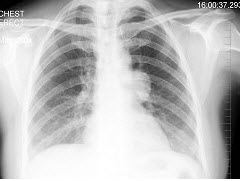

4、单项选择题

患者输液过程中突发胸闷、气急、咳痰,胸片如图,最可能的诊断为()

A.矽肺合并感染

B.中央型肺水肿

C.真菌感染

D.间质性肺水肿

E.腺病毒肺炎

点击查看答案